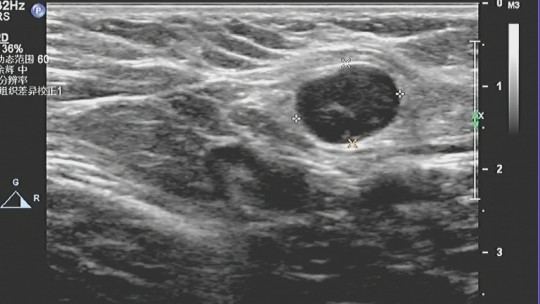

1、肿块多呈不均质的低回声,没有包膜,后方回声可衰减。

2、肿块不规则,会有分叶情况,典型的有“蟹足状”。

3、边界不清,毛刺状边缘。

4、高大于宽,即是纵横比大于1。